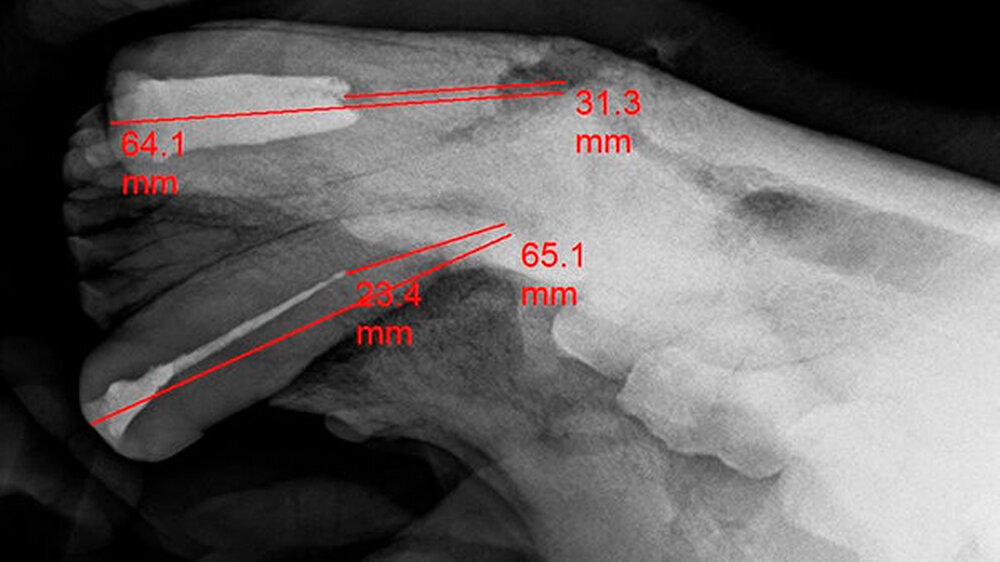

Drittens: Wurzelkanalbehandlungen an den Fangzähnen, den Dentes Canini, bedeuten aufgrund der extremen Länge von 70 bis 80 Millimetern bei großem Kanallumen eine enorme Herausforderung. Sie erfordern einen hohen Aufwand bezüglich der Darstellung und des „Flarings“ des gekrümmten Kanallumens mit Lindemannfräsen (60 Millimeter) und langen Wurzelkanalfeilen (75 bis 90 Millimeter), um die notwendige Arbeitslänge zu erreichen. Die elektrometrische Längenbestimmung funktioniert bei diesen Dimensionen nicht wirklich präzise, so dass man ohne eine Röntgen-Mess-Aufnahme zu einer fehlerhaften Längenabstimmung kommt.

Arbeitslänge: 80 Millimeter